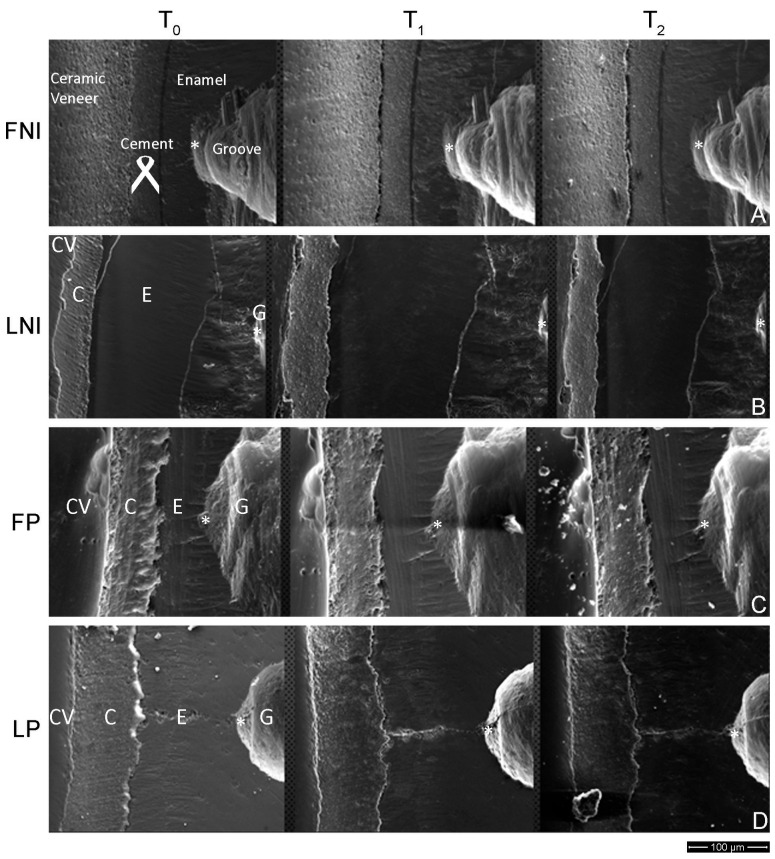

Background/Objectives: To compare the marginal integrity of sectional non-invasive laminate veneers versus sectional minimally invasive laminate veneers. Methods: A total of eighty (80) intact maxillary and mandibular frontal teeth (central incisors) were randomly divided into four groups (n = 20). Two groups received non-invasive veneers made of feldspathic porcelain (Feldspathic Non-Invasive-FNI) and lithium disilicate (Lithium Disilicate Non-Invasive-LNI) accordingly. Groups FP and LP received minimally invasive veneers manufactured by feldspathic porcelain and lithium disilicate, respectively. Following cementation, three grooves with mesio-distal orientation on the labial surface of teeth of each sample, at the incisal, middle, and cervical third, were made. Before and after artificial aging, the mesio-distal distance between the end of the groove on the tooth and the edge of each veneer was measured in micrometers (μm) employing an SEM immediately after cementation (T0), after simulated artificial aging equivalent to four months of everyday brushing (T1), and after twelve months of everyday brushing (2 times per day) (T2) to identify the wear of veneers. In the same manner, the horizontal dimension of the cement layer extending from its edge till the margin of the veneer was measured for all the groups at T0, T1, and T2, respectively. The statistical analysis was performed employing non-parametric Kruskal-Wallis ANOVA and Dunn's test. Results: No significant differences from T0 to T1 and from T1 to T2, as well as from T0 to T2, were identified for all the groups tested. No significant differences were allocated among all groups for the dimensional changes in the cement. Conclusions: All the groups responded similarly to aging factors, regardless of the non-invasive or minimally invasive approach, or the material used to fabricate the veneers.